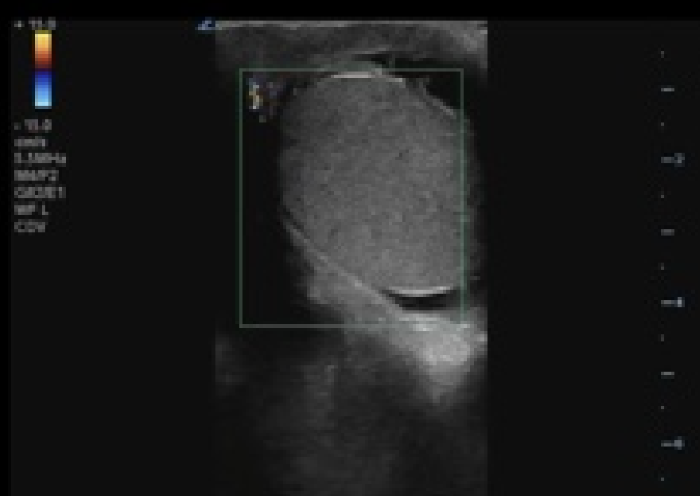

[Image 2. Twisted spermatic cord (“corkscrew sign”) concerning for testicular torsion.

In your first image (Image 1), you realize there is no flow with color Doppler. Additionally, you find a torsed cord complex (Image 2), also known as the “corkscrew sign.” You consult Urology who is busy in the operating room with another case. You decide to perform a manual detorsion due to your concern for testicular atrophy and risk of infertility. Using the open book technique, you get relief of pain and return of vertical positioning of the testicle after two rotations. On your repeat testicular POCUS with color Doppler you obtain these images (Images 3 and 4), which demonstrate venous and arterial flow throughout the testicle. The cord is now untwisted and appears linear in orientation.